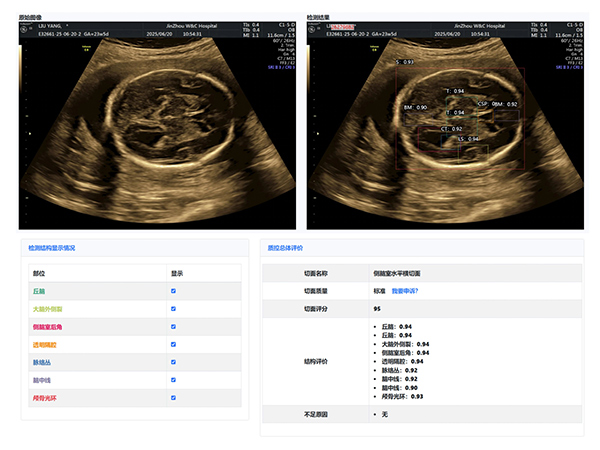

大赛汇聚了超声科全体医生,他们在产科超声领域各展所长。本次大赛引入了产前超声AI智慧云平台作为评分系统。

该平台利用先进的图像识别技术,对参赛的NT、I级、Ⅱ级、Ⅲ级产科超声图像进行精准分析与评分,确保了比赛的公正性与准确性,也体现了医院在医疗领域智能化、精准化的探索与进步。

经过激烈的角逐,年轻医生陈昱在NT产科超声图像评比中,凭借对NT精准的测量荣获第一名,展现出新生力量的专业风采;王斌医生在I级产科超声图像评比中,以精湛技术和对细节的精准把握摘得桂冠;刘芳医生的Ⅱ级产科超声图像作品,凭借清晰的图像质量和准确的诊断信息脱颖而出;Ⅲ级产科超声图像作品的评比竞争尤为激烈,李杭医生以微弱优势获得第一名。

大赛主持人超声科邵雪竹主任总结:“值此中国医师节举办图霸大赛,意义非凡。这不仅是技术的较量,更是我们交流学习的平台。通过活动,我们相互学习,共同提高,为患者提供更优质服务。AI智慧云平台的引入,标志着我院产科超声诊断迈向智能化、精准化。”

锦州市妇婴医院(妇幼保健院)作为锦州市权威产前诊断中心,肩负着对辖区内产前筛查机构(超声产前筛查切面完整率和超声产前筛查切面标准率等)的质控数据进行质量控制,超声科本次大赛初步尝试利用人工智能AI大数据技术开展质量控制与评价,取得了良好的效果。我们将以此为契机不断完善,促进全地区产前筛查服务的标准化、同质化。